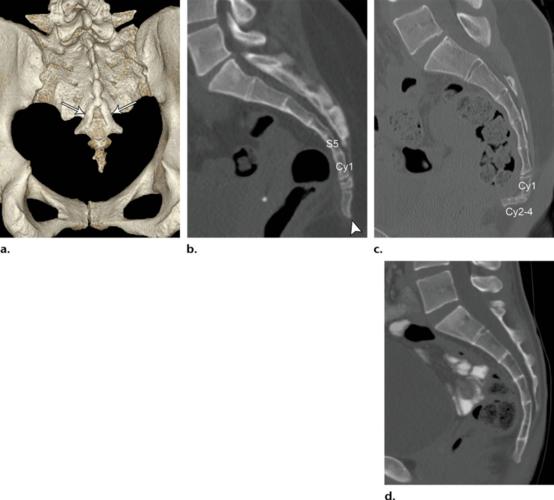

骶尾骨正常变异的影像学分析

正常骶尾骨ct图片

骶尾骨ct图片